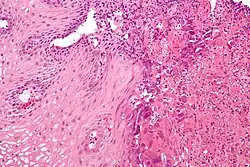

Esofagite Eosinofilica

É uma doença inflamatória com características alérgicas, causada por um denso infiltrado de eosinófilos no epitélio esofágico. O diagnóstico é feito por endoscopia digestiva alta, com identificação de lesões sugestivas e realização de biópsias. A análise destas amostras deve demonstrar a presença de pelo menos 15 eosinófilos por campo de grande aumento. O tratamento baseia-se em dietas específicas bem como medicamentos como corticóides.[1]